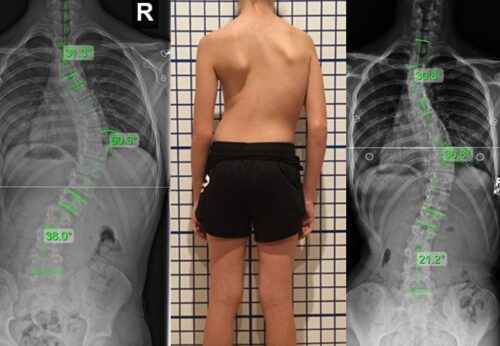

- درجة الانحناء (زاوية كوب)

1. إذا كانت زاوية الانحناء متوسطة

عادة عندما تكون زاوية كوب بين 20 و40 درجة، يكون الحزام هو الخيار الأفضل لمنع زيادة الانحناء.

3. إذا كانت الحالة تتطور بسرعة

إذا لاحظ الطبيب زيادة في زاوية الانحناء خلال فترة قصيرة، فهذا مؤشر قوي لاستخدام الحزام.

كيف أعرف أن طفلي يحتاج إلى حزام اعوجاج العمود الفقري؟

هناك علامات تستدعي التقييم، مثل:

- زيادة ملحوظة في انحناء الظهر

- عدم توازن واضح في الجسم

- اختلاف في مستوى الكتفين أو الحوض

- تطور سريع في الحالة